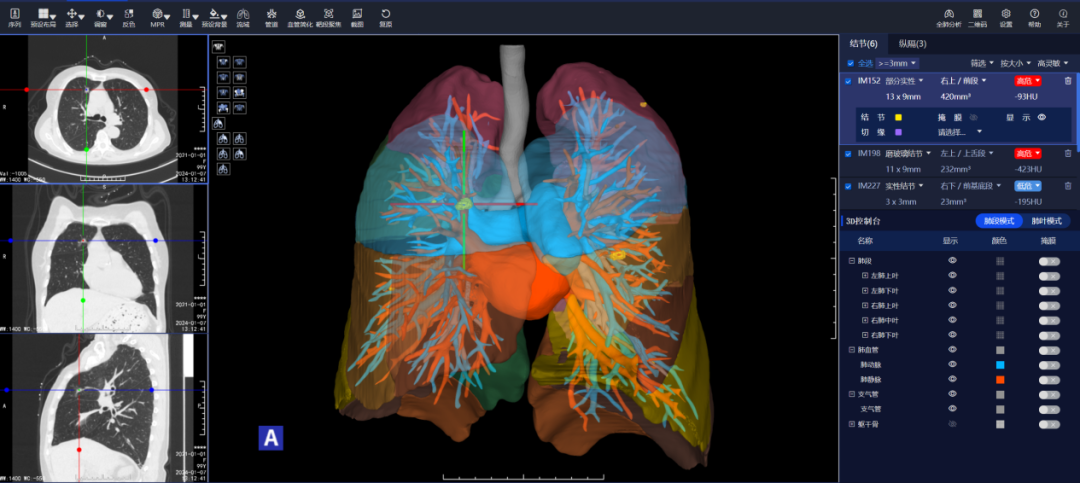

一次感冒,发现双肺结节 患者李女士:“我是由于一次感冒,在老家拍摄胸部CT后发现有双肺结节,后来在家人的陪同下来到市第二人民医院就诊。经过王述波主任团队的手术治疗,顺利地切除了结节,不再担惊受怕了。” 在发现肺结节1个月后,李女士被王述波主任手术团队接诊。团队进行评估发现,该患者CT提示右肺上叶毛刺状结节、左肺上叶混合密度结节,考虑早期肺肿瘤可能性大。(右肺上叶前段结节;左肺上叶上舌段结节) “量体裁衣“精准手术,术后4天康复出院 王述波、王永明主任团队在胸外手术规划系统的指导下,经过术前评估和讨论,决定采取分阶段的手术方案以最大程度地确保手术的成功和患者的安全。 首先,对患者右肺上叶前段采用肺段切除手术进行优先处理。利用系统提供的精准定位功能,准确识别结节周围的血管位置、安全切除范围。术中,在胸腔镜下准确裁剪,保证切缘,确认切除了患者右肺上叶前段肺组织。 最终这例手术过程顺利,术后患者4天康复出院,没有不良反应。(右肺上叶前段病灶阻断血管三维重建图) AI+3D助力手术,消除患者后顾之忧 潍坊市第二人民医院(潍坊呼吸病医院)2024年初引进的3D手术规划系统,为每位患者量身定制了精准的手术方案,在AI+三维重建技术的加持下,为实现精准的肺段及肺亚段切除提供了强有力的支持,达到“量体裁衣”的目的。在术前患者能够清晰了解治疗过程,解除了早期肺癌可能带来的焦虑感,使得治疗过程更加透明和可信。 健康之路,我们与您同行 潍坊市第二人民医院(潍坊呼吸病医院)胸外科是市级医学重点学科,全科医护人员以学科建设、新技术引进和创新为切入点,加强人才培养和引进,现已形成集医疗、教学、科研于一体,具有明显特色和优势的学科。近年来,胸外科开展了气管支气管成形术,肺、食管联合切除手术、单孔胸腔镜肺叶切除、单孔胸腔镜肺段切除、胸腔镜下袖式切除、人工胸骨移植手术、食管癌二切口、三切口,二、三野淋巴清扫等一系列高难度手术,居国内领先水平。由胸外科领衔的肿瘤综合治疗会诊制度,涉及到胸外、呼吸、肿瘤内科、放疗科、放射科等多个专业,对每一位胸部肿瘤患者就诊断、鉴别诊断、治疗及预后等方面进行多学科会诊,受到了全市乃至全省专业同行的认可。咨询电话:0536—8214091/8214109 科普链接 胸腔镜下肺段切除术胸腔镜下肺段切除术,又称胸腔镜下解剖性肺段切除术,采用微创方式将小病变所在的肺段精准切除,在保证肿瘤手术根治的同时,最大限度保留了正常的肺组织,降低了肺功能的损失,实现了真正意义上的微创。